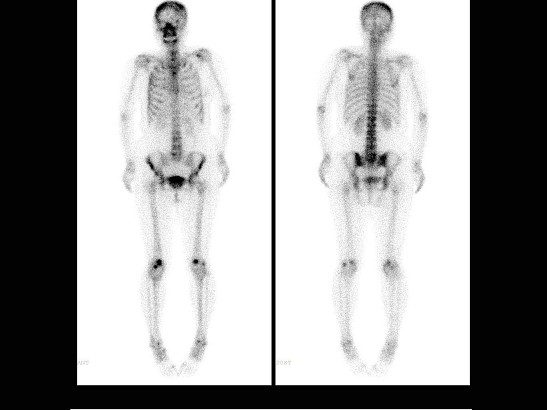

男,36岁,诉晨起酸痛数月,行99Tcm-MDP骨显像如图,对此影像描述正确的是 ( )

多选题 12-10 做题人次:1201